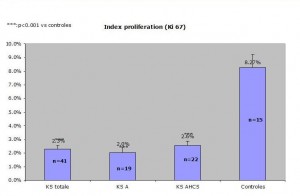

Results: The proportion of Ki-67 positive cells out of all SKS altogether equalled 2.3% +/- 0.3% whereas the one of control skin was 8.27% +/- 0.7%. One of the specimens was subtracted from the study because the proportion of ki-67 positive cells equalled 72%!There was no statistical difference between the two chosen histological types of SK( reticulo-acanthotic 2.0 +/- 0.5% versus acanthohyperkeratotic 2.6% +/- 0.3%. The difference was statistically significant between SK and the control group. The control group divided into two groups, one on inflamed skin and the other on normal skin showed a statistical difference with the inflammatory group showing a bigger percentage of ki-67 positive cells.

Comparaison of reticulo-acanthotic subtype of SK, Acanthohyperkeratotic, these two histological subtypes combined and normal skin. The average normal proliferating skin has an average of ki-67 positive cells of 8.27 percent which is at least 250% of the SK ki-67 percentage of positive cells (2.3%) KStotale=all SKs studied KS A=acanthotic or reticulate SKs KS AHCS=acanthotic and hyperkeratotic SKs Control=control group

Results: The proportion of Ki-67 positive cells out of all SKS altogether equalled 2.3% +/- 0.3% whereas the one of control skin was 8.27% +/- 0.7%. One of the specimens was subtracted from the study because the proportion of ki-67 positive cells equalled 72%!There was no statistical difference between the two chosen histological types of SK( reticulo-acanthotic 2.0 +/- 0.5% versus acanthohyperkeratotic 2.6% +/- 0.3%. The difference was statistically significant between SK and the control group. The control group divided into two groups, one on inflamed skin and the other on normal skin showed a statistical difference with the inflammatory group showing a bigger percentage of ki-67 positive cells.

Comparaison of reticulo-acanthotic subtype of SK, Acanthohyperkeratotic, these two histological subtypes combined and normal skin. The average normal proliferating skin has an average of ki-67 positive cells of 8.27 percent which is at least 250% of the SK ki-67 percentage of positive cells (2.3%) KStotale=all SKs studied KS A=acanthotic or reticulate SKs KS AHCS=acanthotic and hyperkeratotic SKs Controles=control group